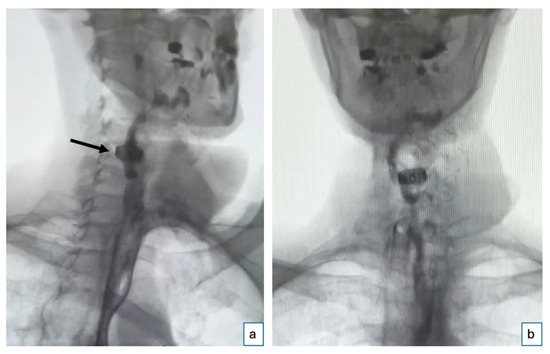

2. Case Report